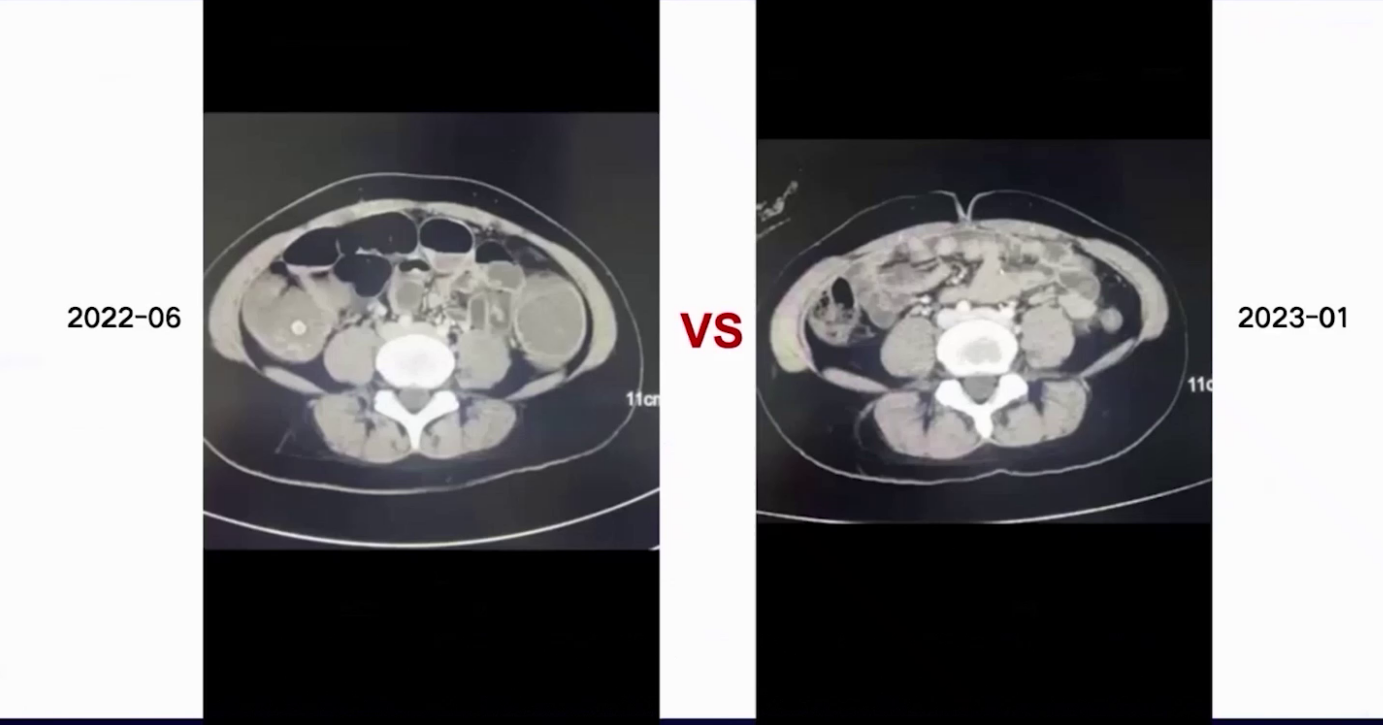

2022年6月到2023年1月,患者共接受12个周期治疗。治疗期间肠梗阻症状逐步改善,无腹胀腹痛,导尿管颜色变清,阴道无粪性液体排出,实验室CEA和CA19-9急剧下降至正常范围。每化疗3周期行一次腹部CT评估,与6月基线相比,肿块持续缩小,周围淋巴结及系膜结节也缩小,疗效评估为PR。